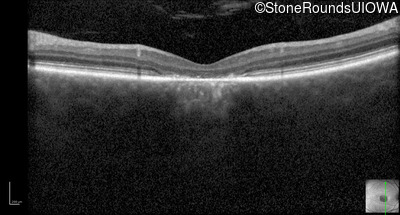

Optical Coherence Tomography - Left - 20/100

Exemplar / OCT Stack